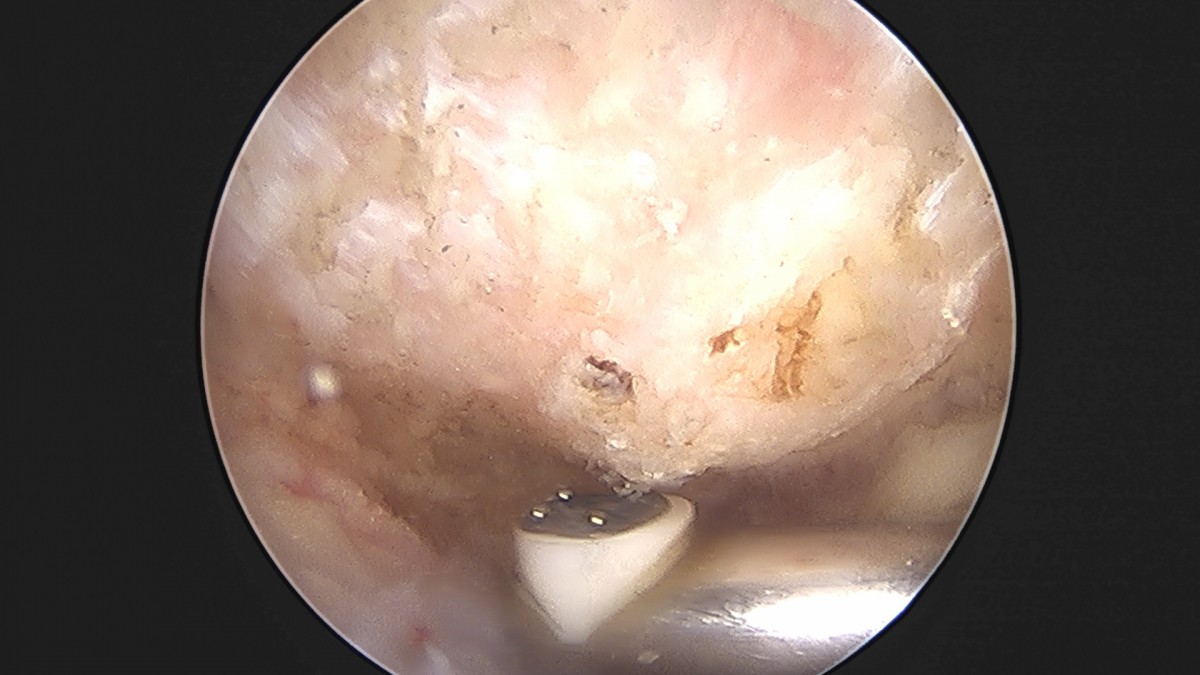

이재상원장님 어깨 견봉하 감압술 이승O 환자

작성자 최고관리자 댓글 0건 조회 806회 작성일 25-09-16 15:26